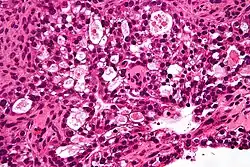

| Micrograph of a mucinous ovarian carcinoma stained by H&E | |

Mucinous

Mucinous tumors include mucinous adenocarcinoma and mucinous cystadenocarcinoma.[29]

Mucinous adenocarcinoma

Mucinous adenocarcinomas make up 5–10% of epithelial ovarian cancers. Histologically, they are similar to intestinal or cervical adenocarcinomas and are often actually metastases of appendiceal or colon cancers. Advanced mucinous adenocarcinomas have a poor prognosis, generally worse than serous tumors, and are often resistant to platinum chemotherapy, though they are rare.[29]